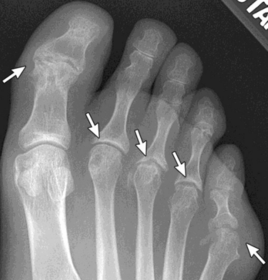

What disease is this? | Gout |

What disease is this? What do the arrows indicate? | Gout Arrows = 'punched out' erosions |